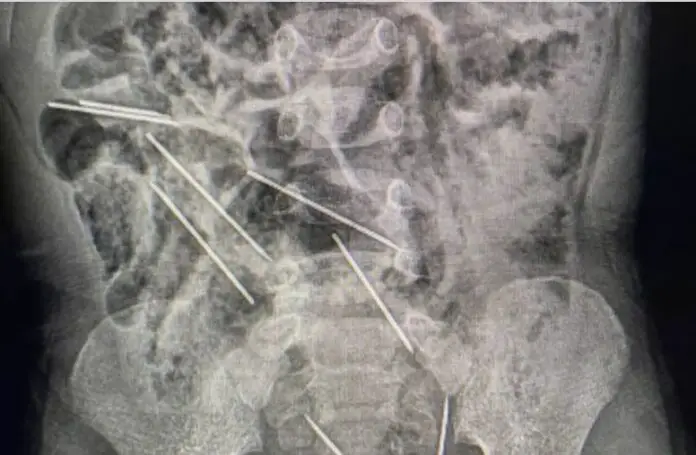

Los profesionales de la salud se enfrentaron una labor complicada, ya que las agujas se encontraban dispersas en diferentes partes del estómago y el tracto intestinal del niño.

La extracción de las agujas duró aproximadamente dos horas. Según los médicos, una vez que abrieron el abdomen del niño, localizaron fácilmente “los cuerpos metálicos”. Dos de las agujas se encontraban en el peritoneo del lado derecho, una había ingresado en el epiplón, tres en el lado izquierdo, una en la pared abdominal y dos peligrosamente ubicadas entre la vejiga y el recto, detalló uno de los médicos.